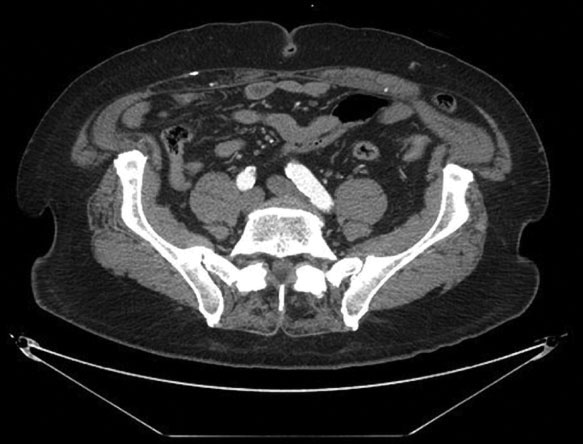

Spigelian hernias usually have narrow orifices, between 0.5 and 2.5 cm in diameter.10 This contributes to their high incidence of incarceration and strangulation. Figure 3 demonstrates the different sizes of two, left-sided Spigelian hernias; both hernias penetrate all the way to the external oblique aponeurosis. The smaller hernia, seen on the left, contained only fat; the larger hernia, seen on the right, contained both colon and omentum. A computed tomography (CT) scan of the larger hernia, seen on the right, is demonstrated in the diagnostic portion of this chapter.

In Figure 4, notice the colon, marked by the arrow, as it passes through the Spigelian fascia just lateral to the left rectus muscle and becomes entrapped below the external oblique fascia. More inferiorly on the CT scan, in Figure 5, the internal oblique and transversus abdominis muscles can also be seen deep to the hernia, near the iliac crest.